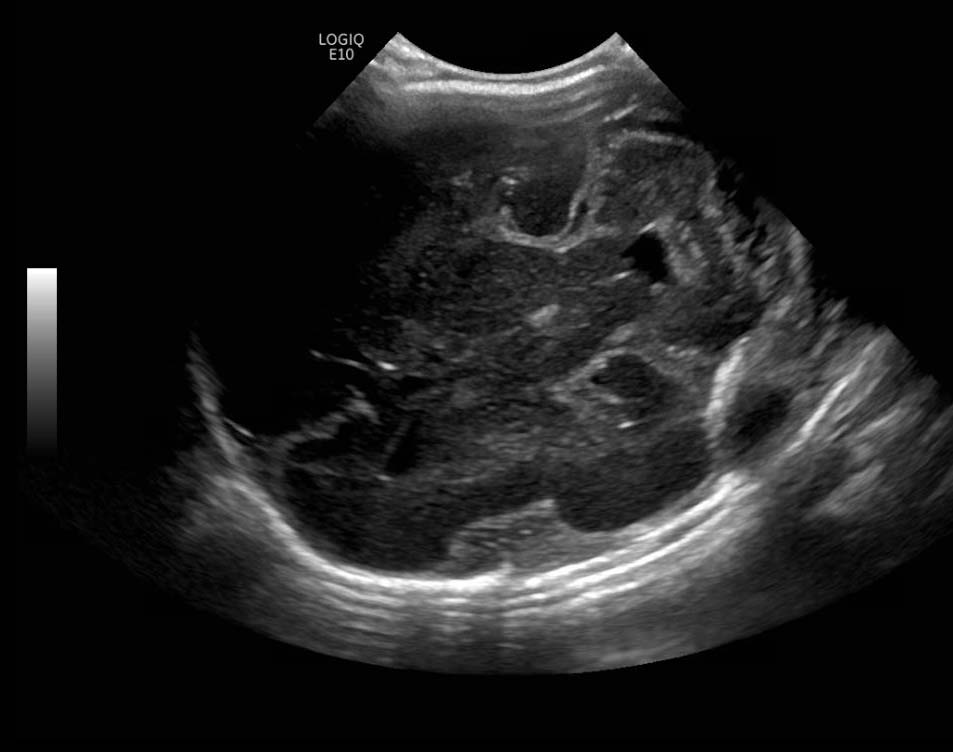

Age: 4 days (born at 24 weeks)

Sex: Male

Indication: Evaluate for germinal matrix hemorrhage

Grade 2 germinal matrix hemorrhage

Sample ReportLeft germinal matrix hemorrhage involving the caudothalamic groove and layering in the occipital horn of the left lateral ventricle without hydrocephalus (grade 2).

No abnormal brain parenchymal echogenicity or extra-axial collections.

Premature sulcation pattern.